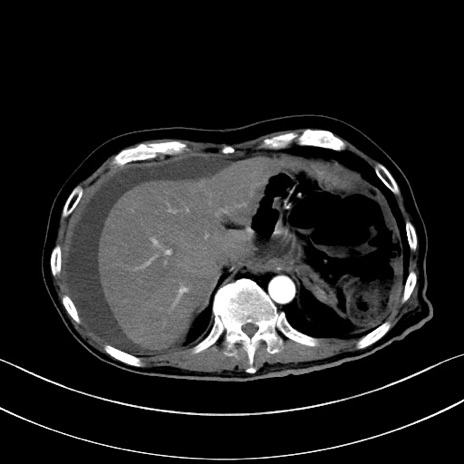

症例28(横断像)

【症例】60歳代男性

【主訴】嘔吐

【現病歴】胃癌にて胃全摘後。食思不振が悪化し、夜中に嘔吐することがある。

【既往歴】胃癌、胃全摘、脾摘、胆摘後

【データ】WBC 5900、CRP 10.56